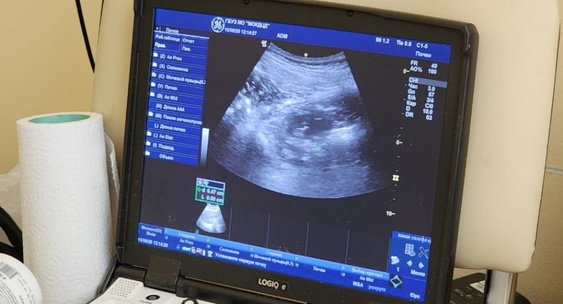

Быстро растущее использование препаратов — агонистов рецепторов GLP-1, применяемых при диабете и для снижения веса, может искажать результаты онкологических ПЭТ-КТ-исследований.Lenta.ru

Исследователи отметили повышенное накопление препарата в мышцах, сердце и бурой жировой ткани — эффект, который может быть ошибочно принят за опухоль или воспаление.Lenta.ru